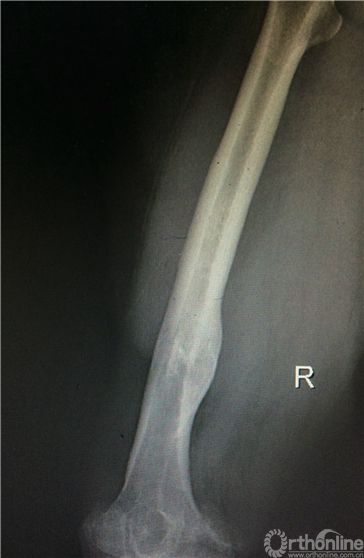

患者女性,69岁,病史7年。表现为逐渐加重的右膝关节疼痛、活动受限,负重行走和劳累后出现,上下楼梯更重,初始休息后可缓解,经口服硫酸氨基葡萄糖,非甾体类消炎药物,及“小针刀”,关节内注射玻璃酸钠等多种保守治疗,3年前疼痛、活动受限明显加重,影响日常生活就诊。23年前车祸伤致右股骨中下段粉碎骨折,外院行切开复位内固定,术后7月内固定松动,骨折未愈合,遂再次行切开复位内固定,髂骨取骨植骨术,直至骨折愈合后1年取出内固定。有高血压病史,规律服用降压药物控制良好。患者身高153cm,体重85公斤,BMI36kg/m2。右膝外上25cm术后瘢痕,右膝活动度10-90度,膝内外侧均有压疼,髌磨阳性。术前全长X片,膝关节负重正侧位片提示右膝关节重度骨性关节炎,右股骨中下段成角畸形(图1a,1b,1c)。

图1a. 双下肢全长片,右膝重度骨性关节炎,右股骨中下1/3陈旧骨折畸形愈合,向内侧成角畸形。

图1b. 右股骨中下段内侧成角畸形,股骨外翻角约14度。

图1c. 矢状位显示股骨中下段无明显成角畸形。